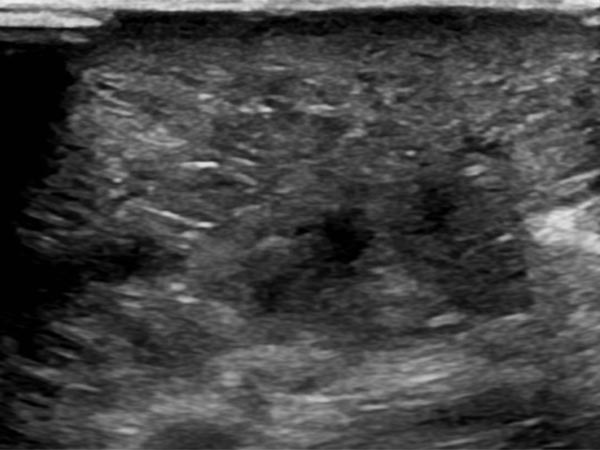

In der B-Bild-Sonographie des subkutanen Anteils der LM zeigt sich ein dysplastisch erweiterter Lymphkanal als echofreie tubuläre Struktur. Das umgebende subkutane Fettgewebe ist deutlich echoreicher als normal durch die eingelagerte Flüssigkeit.

In der B-Bild-Sonographie (Querschnitt proximaler ventraler Oberschenkel) zeigt sich ebenfalls das deutlich echoreiche Gewebe, von einzelnen sehr feinen, dilatierten flüssigkeitsgefüllten Lymphleitern durchsetzt.